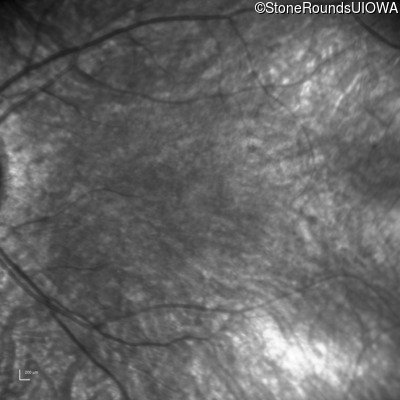

Age at visit: 10 years

Age at visit: 12 years